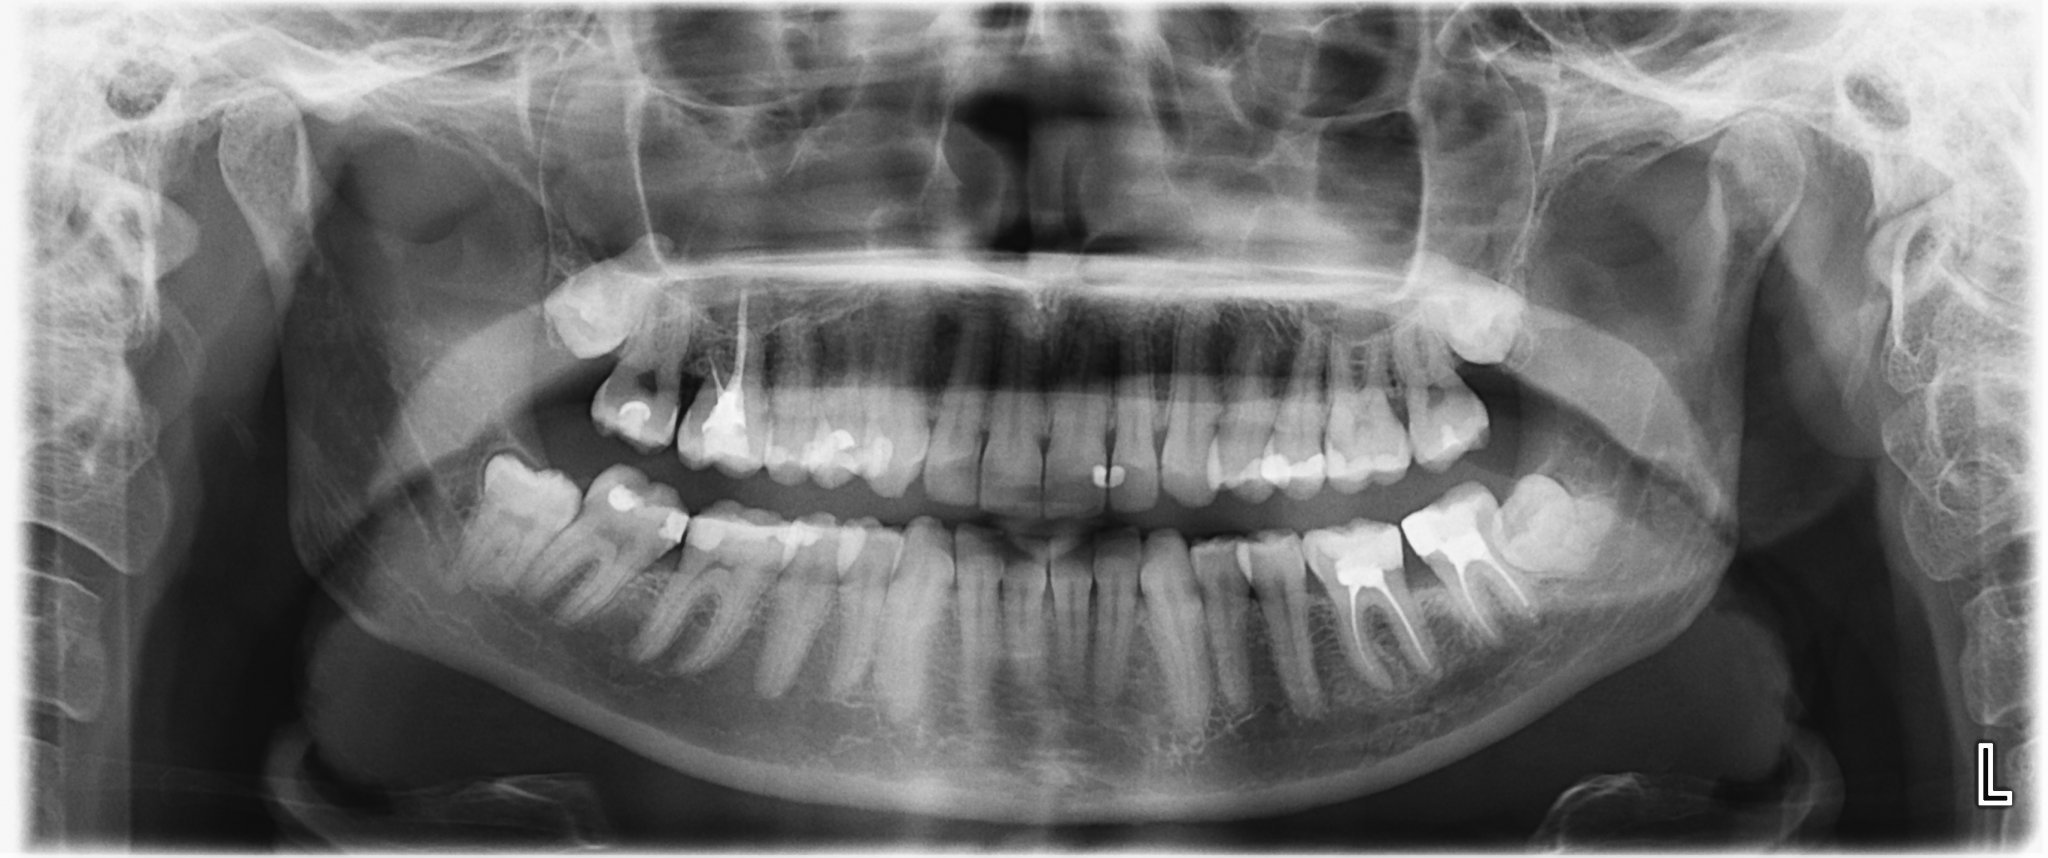

Прилагам снимка.

46ти зъб долу със сигурност е фатално зле,но се надявам да може да се спаси.

Освен това е възможно болката да се дължи и на зъби,които вече са правени от 3ма стоматолога преди 2 год и пак....не са направени добре........(16 ти и 17ти зъб)

След това заради тях съм ходила при доста хвалени ендодонти просто на преглед,за да ми кажат за прелекуване ли са или не и така и категорично никой не ми каза.

Въпросите са ми дали е възможно сега да имам болка от някои от тези зъби?

Възможно ли е да не е от тях,а да е от стискането на зъбите?

Кой зъб е най-спешен за правене и важно ли е да е направен от ендодонт?